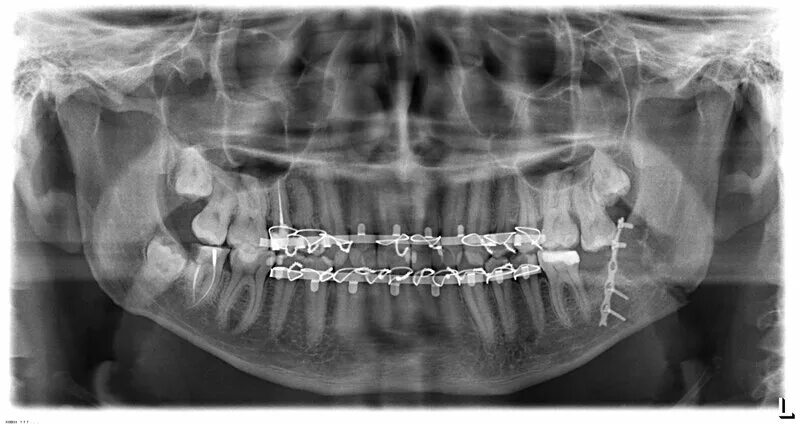

Переломы челюстей студфайл